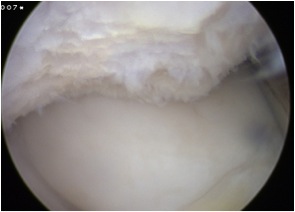

Arthroscopy

Chondral damage capitellum Chondral damage radial head Chondral damage ulnohumeral joint